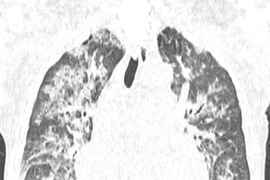

Tổn thương phổi - nguyên nhân hàng đầu gây tử vong liên quan tới truyền máu

Ở Anh với khoảng 2 triệu lượt truyền, đã ghi nhận 59 ca tử vong liên quan tới truyền máu. Hơn một nửa trong số đó liên quan tới các tổn thương ở phổi.